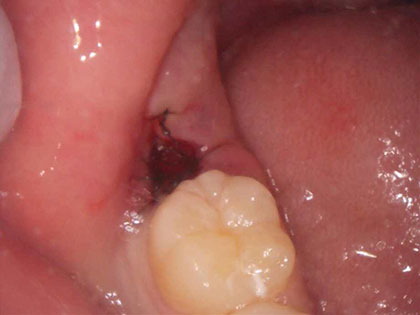

抜歯後の写真がこちら

左右それぞれ歯が萌出中(歯肉を突き破って歯がでてきている)

左下は器具をひっかけると、すぐ歯が脱臼して抜歯出来ます。

右下は少し歯肉を切開し、歯冠(頭の部分)を削り、歯根(根っこの部分)を引っ張りだして抜歯しました。

最後に洗浄し、糸で縫い止血しました。